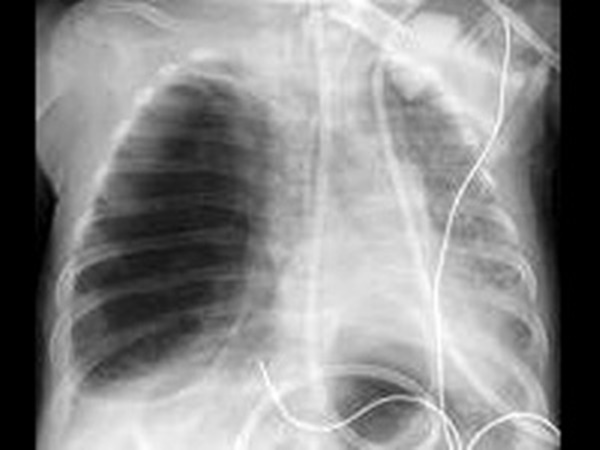

இதற்கு பெரும்பாலும் பயன்படுத்தப்படுவது மால பரிசோதனைதான். அதுதவிர எண்டோஸ்கோபி, சிடி ஸ்கேன், எம்ஆர்ஐ ஸ்கேன், எக்ஸ்ரே போன்றவற்றை பயன்படுத்தியும் கண்டறியலாம்.